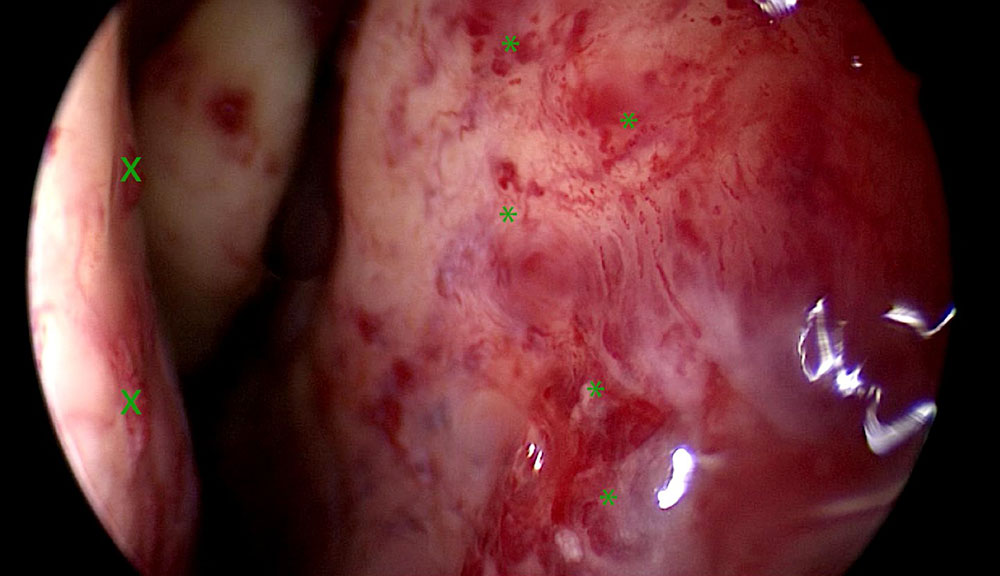

The vascular changes that develop on the basis of the genetic alterations in HHT can be very small in the form of dilated microvessels or several centimeters in diameter in the form of arteriovenous malformations (AVM) or fistulas. They occur in clusters at certain sites in the vascular system. Osler’s disease spots of the nasal mucosa can be identified clinically with relative certainty despite their various manifestations. Nasal endoscopic images show typical spots and their distribution in the nose.

Raised and flat, tangle-like and radially arranged vessels are found in the nose, usually with a bright red color. They may become confluent or appear as well-circumscribed lesions.

Video: Rhinoscopy of a nose with Osler spots of different degrees of maturity © Kühnel